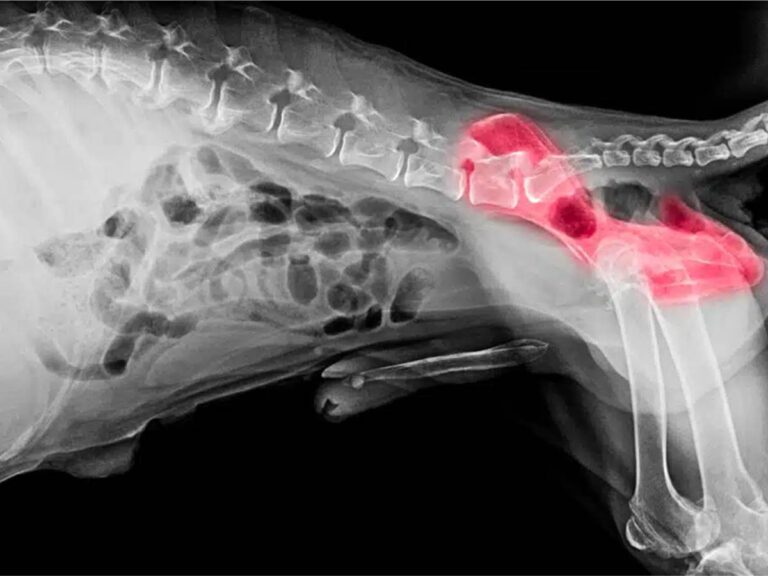

JPS is a minimally invasive surgical procedure designed to modify the growth of the pelvis in young puppies. By fusing part of the pubic symphysis (the cartilage connecting the two halves of the pelvis), this surgery encourages the hip socket to develop a tighter fit around the femoral head, reducing joint laxity and improving stability.

In dogs with hip dysplasia, the hip socket is too shallow, causing the femoral head to shift and grind against the joint improperly. Over time, this leads to arthritis, pain, and mobility issues. By altering pelvic development, JPS improves joint congruity and reduces stress on the hip joint, preventing these issues before they start.

- Pre-Surgical Evaluation: X-rays or PennHIP imaging confirm the degree of hip laxity.